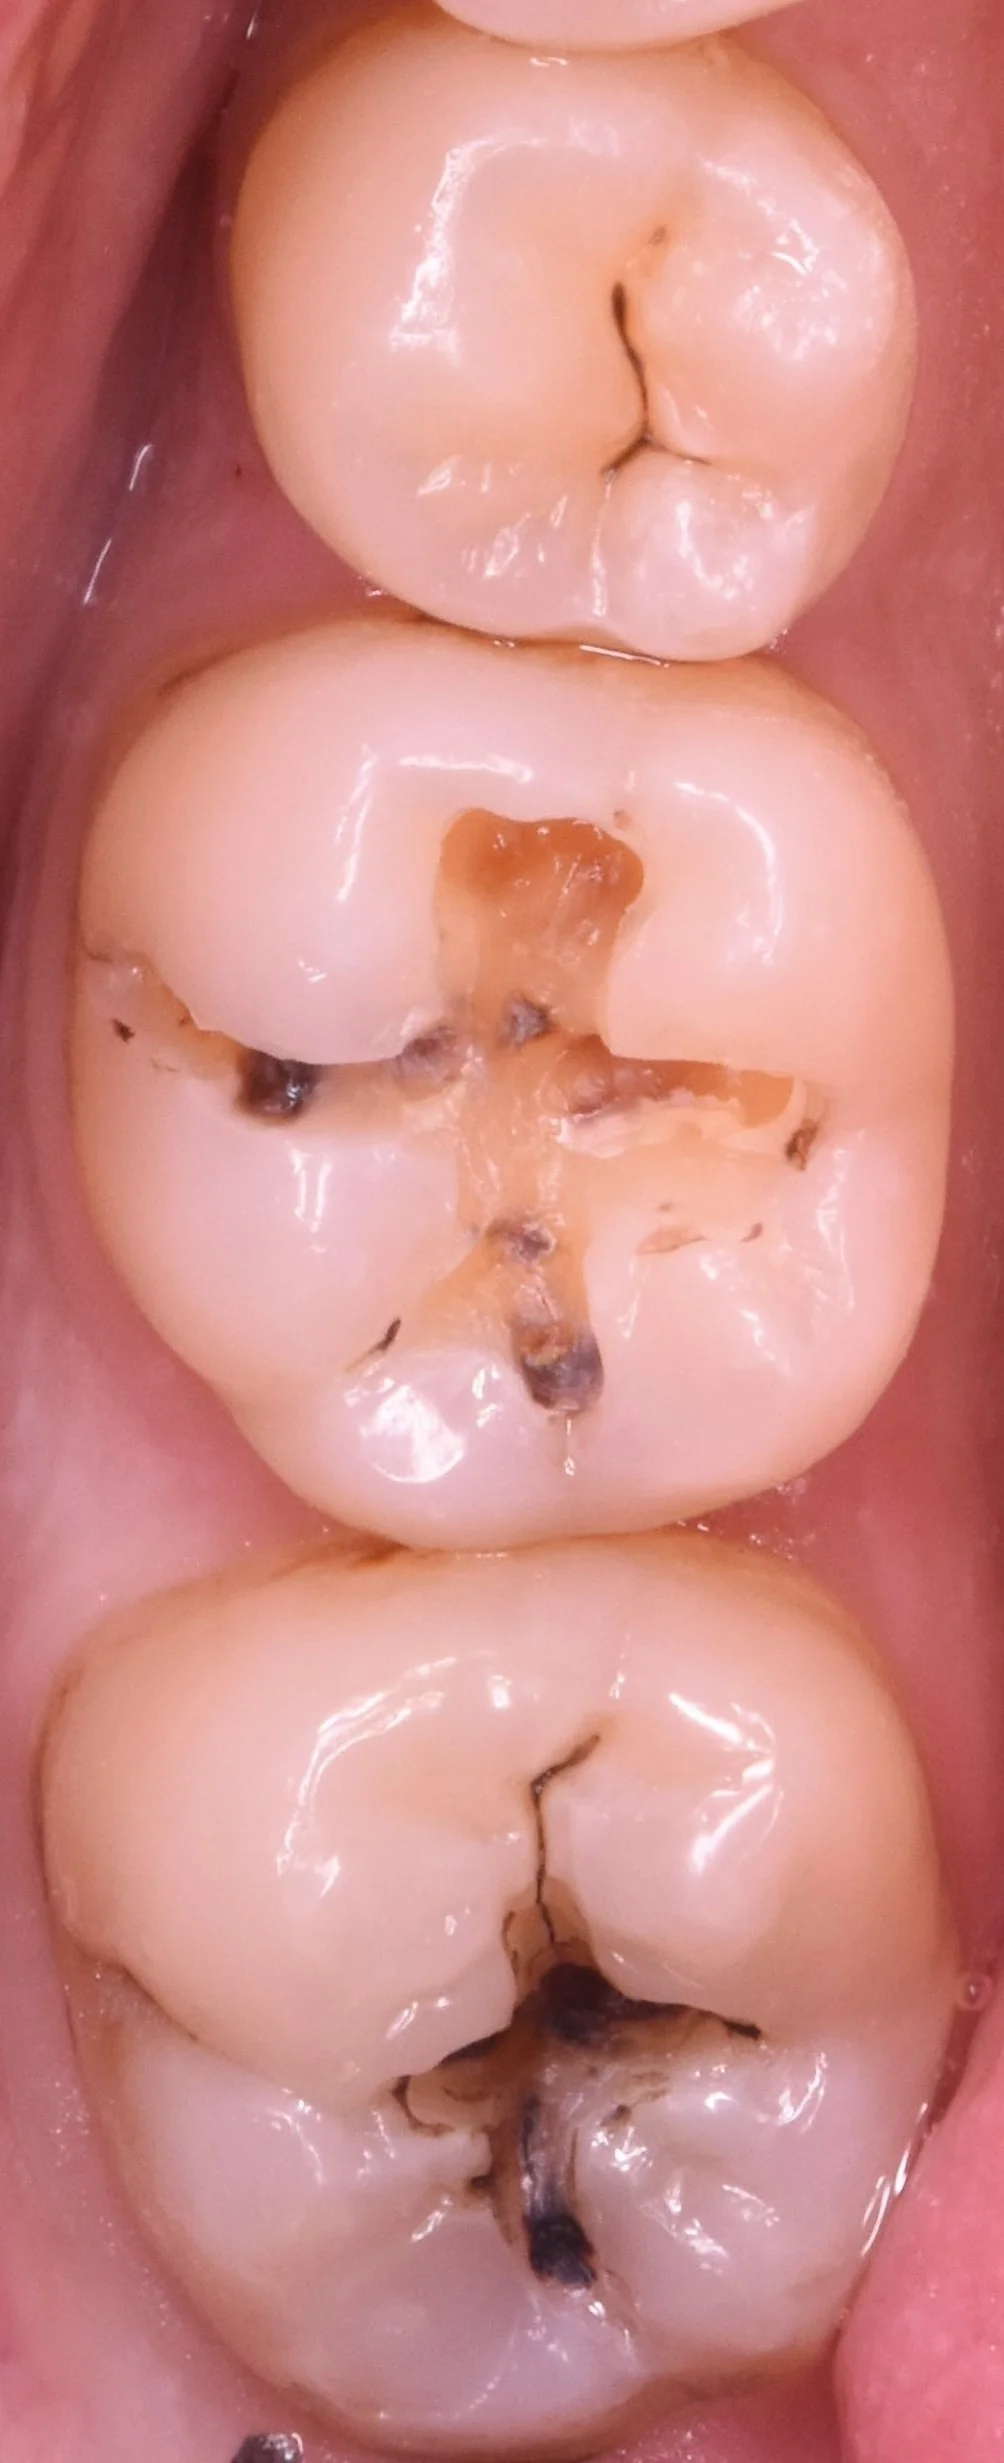

では術前の写真からです。

画像内左側の2本が今回手を付ける部位になります。

金属の詰め物・白い詰め物がそれぞれ入っていますが、黒い部分がすでに目立っていますね。

形を見る限り、それぞれの詰め物がかけた場所から内面に虫歯が入り込んでしまったようです。

金属と白い詰め物のみを除去したのがこちらになります。

表立って見えていた部分は実はそこまで深くなく、別の場所のほうが深い状況でした。

レントゲン上でも見えていたので、もちろん術前の診査である程度の予測がついている状態ではありますが・・・

(レントゲンでのう蝕検出率は最も高いといわれている咬翼法ですら50%前後です。

そのため、レントゲンだけで神経の治療の有無や虫歯の治療の有無・歯を抜くべきかどうかの判断することはできないです。)

実際に見ると相当深くなっているという予測が簡単にできる状況でしたね。

虫歯を取り切ったのがこちらになります。

ところどころ色がついてしまっている場所がありますが、ここは虫歯ではない部分になります。

通常はこの場所も綺麗に取り切ったほうが接着としては有利になるため、術後疼痛や予後がよくなるのですが・・・今回は深すぎたため、ここを取り切ると神経に到達してしまう危険性があったため、可及的に除去し温存しておくこととしました。